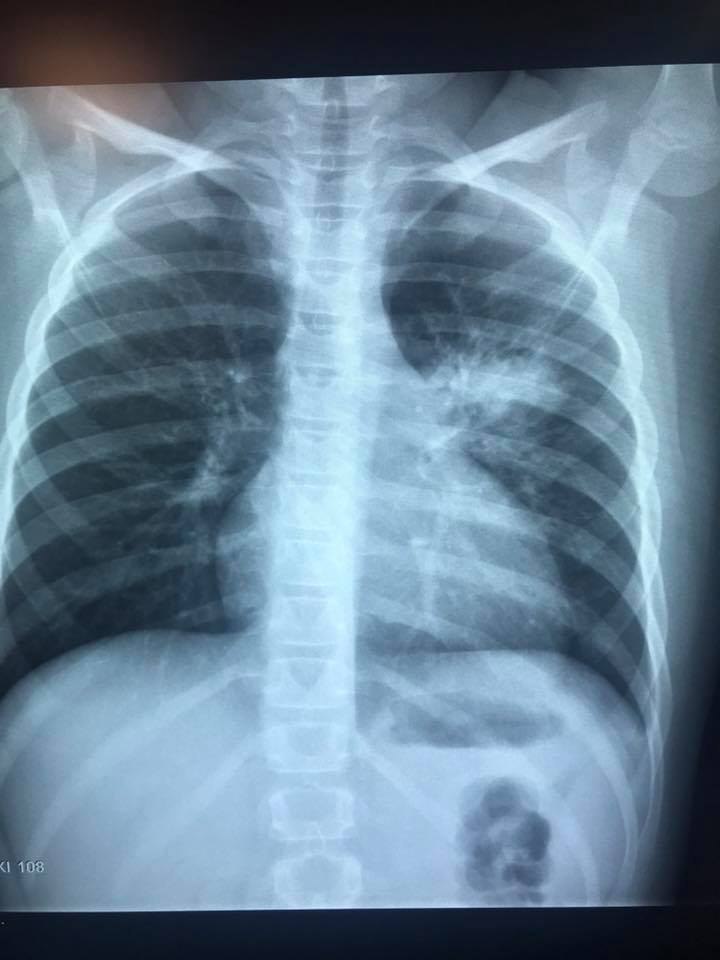

Ну и, чтобы закончить тему, кто желает получше разбираться в рентгенограммах грудной клетки, рекомендую книгу

Заказал, еще не пришла, но доктор Белозерова плохого не посоветует